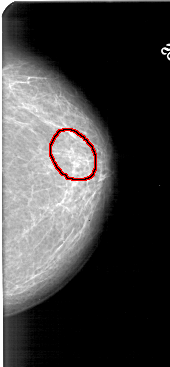

A_1433_1.LEFT_CC

LEFT_CC LINES 4861 PIXELS_PER_LINE 2176 BITS_PER_PIXEL 12 RESOLUTION 43.5 NON_OVERLAY

FILE: A_1433_1.RIGHT_CC.OVERLAY

TOTAL_ABNORMALITIES 1

ABNORMALITY 1

LESION_TYPE CALCIFICATION TYPE PUNCTATE DISTRIBUTION SEGMENTAL

ASSESSMENT 2

SUBTLETY 3

PATHOLOGY BENIGN

TOTAL_OUTLINES 1

BOUNDARY